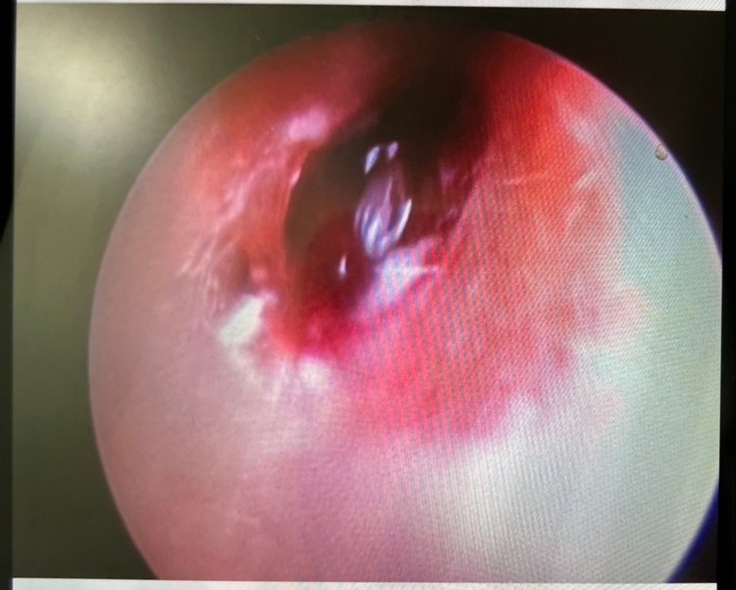

耳の中を見ると大きな出来物?が見受けられたとのことで肉腫なのか異物なのかを確認してから、焼きながら切除とのことでした。

手術の結果としては外耳に腫瘍がありそちらを少しずつ取り除いていただきました。

一枚目は手術前、2枚目は切除あと。

ただ問題は鼓膜近くの見えている外耳の腫瘍ではなく、その先。つまり鼓膜の中、中耳の鼓室から腫瘍が派生していると思われるとのこと。

鼓膜を破っての腫瘍の派生とのこと。